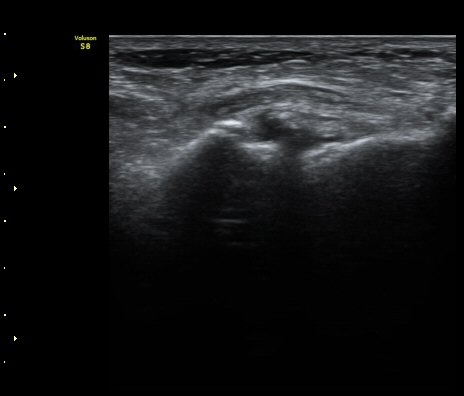

ÃÊÀ½ÆÄ °Ë»ç

Á¾°ñÀÔ¹æ°ñÀδëÀÇ Á¾´Ü¸é°Ë»ç¿¡¼­ ÀδëÀÇ Á¾°ñ ºÎÂøºÎ ÆÄ¿­ÀÌ °üÂûµÊ(»çÁø 1, 2, 3).